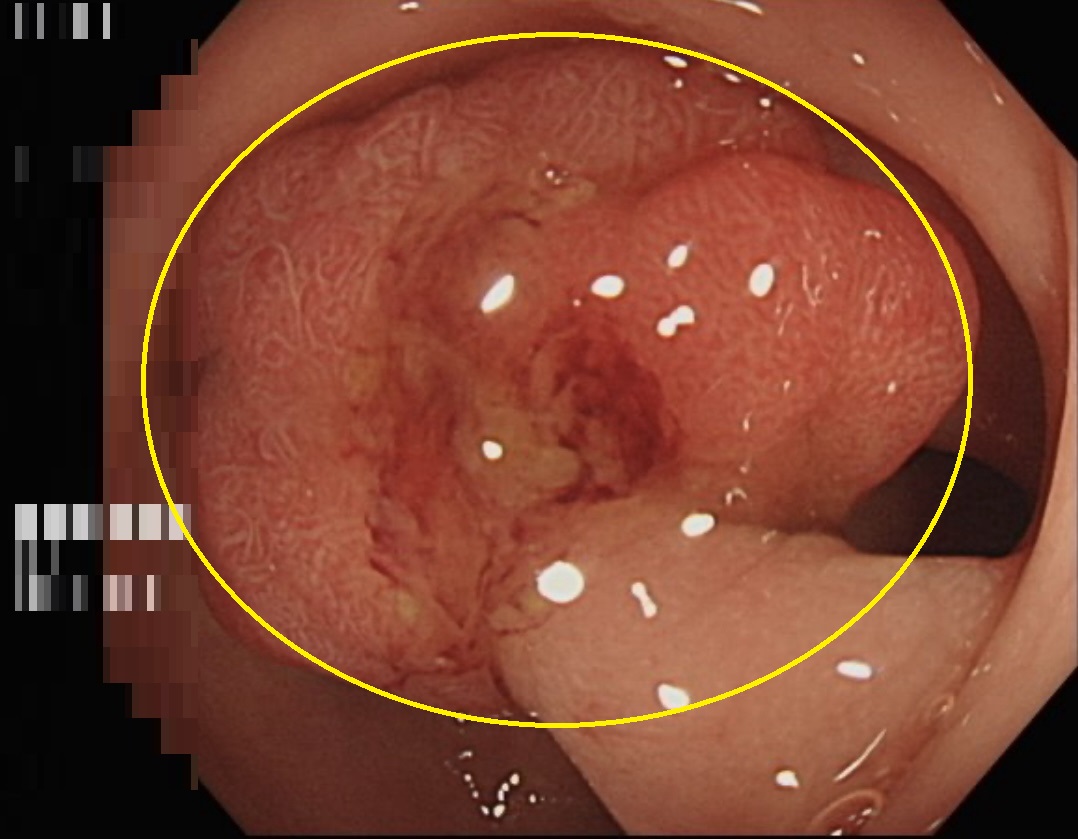

台中一名50歲林姓婦女在糞便潛血篩檢中呈現陽性反應,隨即至長安醫院肝膽腸胃科門診接受檢查。透過大腸內視鏡發現在乙狀結腸處有一個1.5公分大小的瘜肉。

許鈺銓醫師表示,這位病患因為糞便潛血篩檢陽性反應前來就診,詢問病史及理學檢查並無其他異狀。但陽性反應意味著大腸內可能存在息肉或腫瘤,為確保安全,安排了大腸內視鏡檢查,最終發現在乙狀結腸處有一個1.5公分大小的瘜肉。當場進行了瘜肉切除手術,並安排後續回診。

兩週後,病理報告確認該瘜肉為黏膜內腺癌,俗稱大腸原位癌。許醫師解釋,原位癌是最早期的癌症,此時癌細胞僅存在於表層黏膜,尚未侵入其他組織。只要及早發現並切除,患者就能避免後續的開刀、化療等復雜治療。好消息是切除後檢查顯示瘜肉邊緣無殘存癌細胞,表示已清除乾淨,經過解釋及衛教,病患六個月後再接受大腸內視鏡追蹤即可。